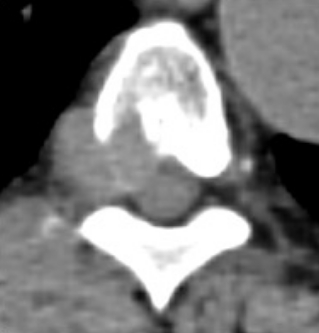

転移性脊髄圧迫とは

週末・連休中も放射線治療が行えるよう、県内3施設で輪番制を開始しました。転移性脊髄圧迫が疑われる場合は、下記をご参照のうえご相談ください。